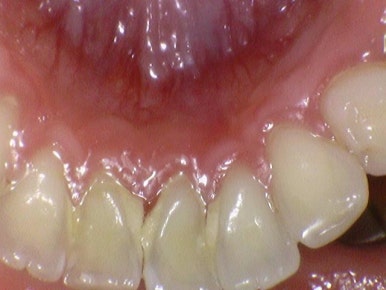

스케일링은 잇몸상방 치석제거 이므로

잇몸속에도 쌓인 치석이 있다면 잇몸치료 꼭 받으셔야 합니다!

잇몸치료도 건강보험 적용됩니다.

스케일링,잇몸치료, 앞니 크라운2개 전후